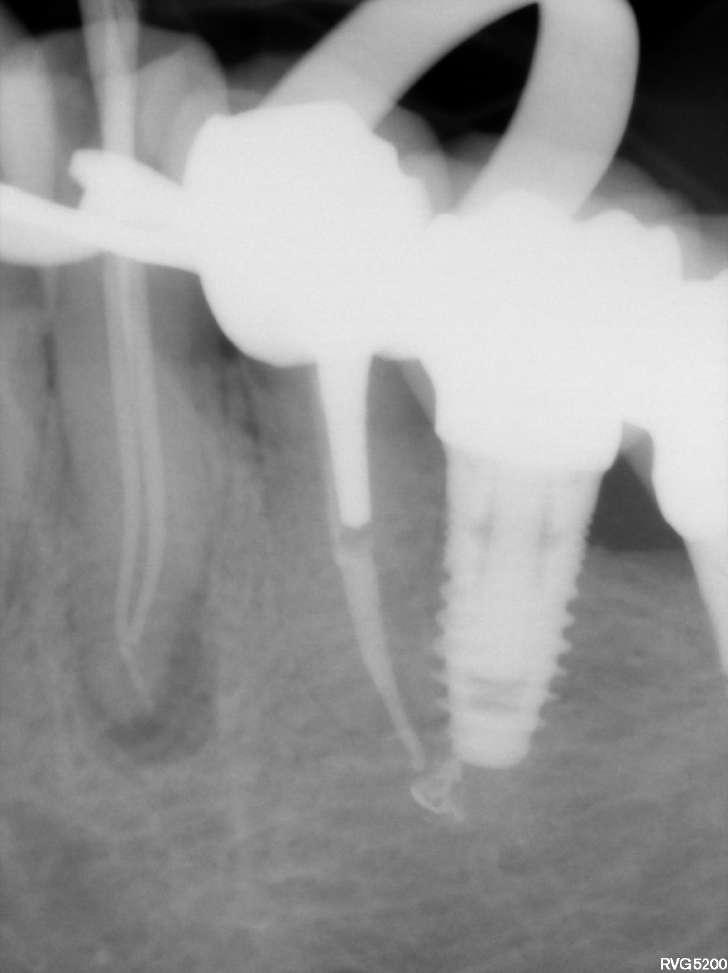

Divergierende Kanäle (zwei Kanäle, die zusammen beginnen und sich dann im mittleren / apikalen Teil der Wurzel trennen) stellen ein klinisches Problem in der Endodontie dar, insbesondere bei der Verwendung traditioneller NiTiInstrumente. Aufgrund des superelastischen Verhaltens der Legierung können die Instrumente dem gleichen Kanal folgen (und zwar dem, der gerader ist) aber es ist schwieriger, den zweiten zu finden, insbesondere dann, wenn man den Eingang unmöglich wegen seiner Tiefe in der Wurzel sehen kann.

Der vorliegende Fall zeigt den klinischen Vorteil der Verwendung einer Einzelfeil-Reziprokationstechnik mit einer wärmebehandelten vorgebogenen martensitischen Feile (Edge One Fire) bei der Behandlung divergierender Kanäle auf.

Untere Prämolaren können manchmal zwei oder drei Kanäle aufweisen. Eine solche ungewöhnliche Anatomie ist oft mit engen, stark gekrümmten, konfluenten oder divergierenden Kanälen verbunden. Der letzte Fall ist sehr komplex und erfordert in der Regel den Einsatz von Instrumenten, welche in zwei verschiedenen Kanälen ( daher flexibel und präbendal ) mit unterschiedlichen Winkelstellungen ausgerichtet werden können. Ein angemessener Gleitpfad hilft auch bei der NiTi-Formung, er löst aber nicht immer das Problem. Daher wurde im vorliegenden Fall die primäre EinzelfeileReziproziertechnik EOF verwendet. Die Instrumente wurden in ihrem apikalen Teil vorgeformt, in die beiden verschiedenen Kanäle eingeführt und dann aktiviert. Die Wahl der Instrumente war effektiv, weil die mechanischen Eigenschaften des EOF-Primärs (flexibel und vorgebogen) es ermöglichen, präzise und einfach in jeden Kanal eingeführt zu werden und diese dann zu behandeln. Die Verwendung einer einzigen Feiltechnik ermöglichte es, sich der Herausforderung eines divergierenden Kanals nur einmal zu stellen, was Zeit spart und die Komplexität reduziert. Die Verwendung traditioneller Instrumente kann in vielen Fällen helfen, den Weg mit kleineren und flexibleren Instrumenten zu finden, aber nicht mit größeren. Durch die Verwendung von nur einer Feile erwies sich das gesamte Verfahren als einfacher und schneller, sodass beide Kanäle korrekt geformt, gereinigt und abgedichtet werden konnten.

Eine Single-File-Reziprozierungstechnik mit einer wärmebehandelten vorgebogenen martensitischen Feile (Edge One Fire) erwies sich als ausgezeichnete, einfache und schnelle Option für die Instrumentierung von divergierenden Kanälen.

Komplexe Kanalanatomien erfordern den rationalen Einsatz von NITIInstrumenten, indem die beste Option für den Fall in Bezug auf Effizienz, Sicherheit und Einfachheit ausgewählt wird. Die mechanischen Eigenschaften von EOF ermöglichen es, divergierende Kanäle mit großer Wirksamkeit zu behandeln, wobei iatrogene Fehler oder Komplikationen vermieden werden können.